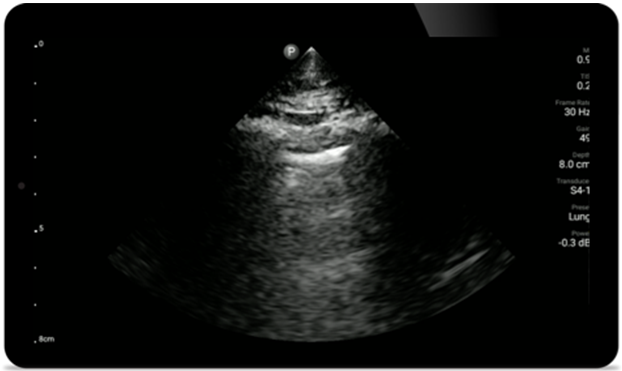

Используйте Lumify для оценки дыхательных путей и легких

Решения Lumify POCUS могут помочь определить положение эндотрахеальной трубки в трахее, помочь в процедурах крикотиротомии, диагностировать плевральный выпот и интерстициальные альвеолярные заболевания.